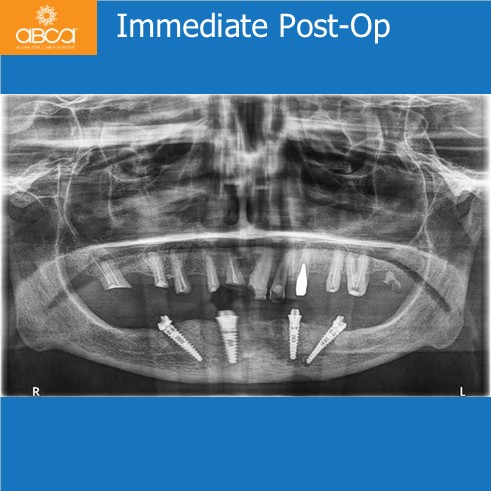

The patient presented with a severe bone defect involving the inferior alveolar canal and mental foramen, with limited bone height and high risk of nerve injury. Using Augma Bond Apatite® to fill in the defects, restore bone volume and enhance implant stability. At six months, new bone fully integrated around stable implants, providing strong biological and mechanical support. After eight years, bone volume remained preserved with no significant resorption, confirming Augma’s long-term success in transforming a high-risk defect into a predictable, stable rehabilitation.